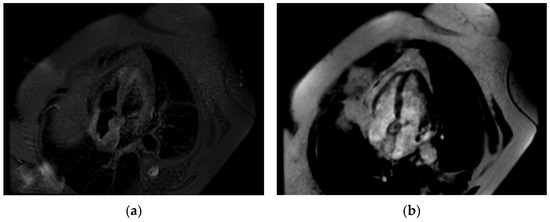

Even though the diagnosis was suspected, a cardiac magnetic resonance was performed in order to be accurate, given the implications a wrong diagnosis might have had. The “hourglass” aspect of the IAS with significant hypertrophy was confirmed in the cine-balanced steady-state-free precession (bSSFP) sequences. There was no contrast up-take at this level, suggesting a lack of vascularization, and the structure showed a high signal in T1 and a low/isointense signal in T2 with a very similar aspect to the very well-represented pericardial and mediastinal fat (Figure 4, Figure 5 and Figure 6). The diagnosis of lipomatous hypertrophy of the interatrial septum was established.

Figure 4.

Cardiac MRI. (a) Four-chamber-view, steady-state-free precession image revealing interatrial septal hypertrophy—25 mm with “chemical shift”; (b) perfusion image—no caption of contrast at first-pass contrast.

Figure 5.

Cardiac MRI. (a) Double-inversion-recovery T1 sequence (4 chambers) revealing a hyperintense interatrial septum suggestive of fat; (b) double-inversion T1 sequence with fat suppression revealing a hypointense interatrial septum.

Figure 6.

Cardiac MRI. (a) Triple-inversion-recovery T2 sequence of isointense interatrial septum; (b) late gadolinium enhancement (LGE)—enhancement in interatrial septum.